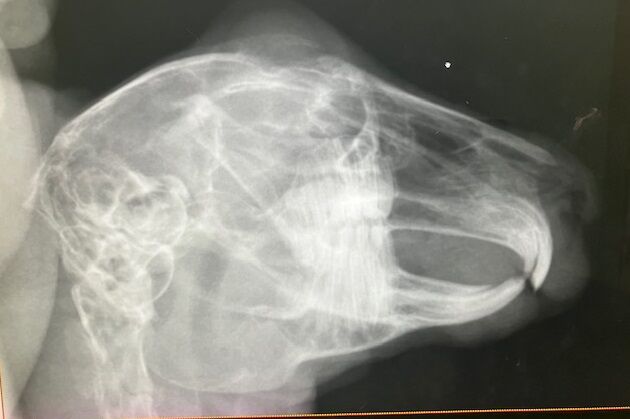

術前検査の血液検査、レントゲン、特に問題ありませんでした。

※多少の差異はストレス起因と判断、

血小板は機械の誤作動により別途顕微鏡で確認済

奥歯のチェックも問題なし。